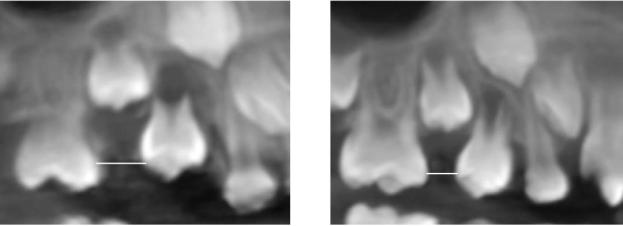

适用于第二乳磨牙早失、第一恒磨牙尚未萌出或萌出中。